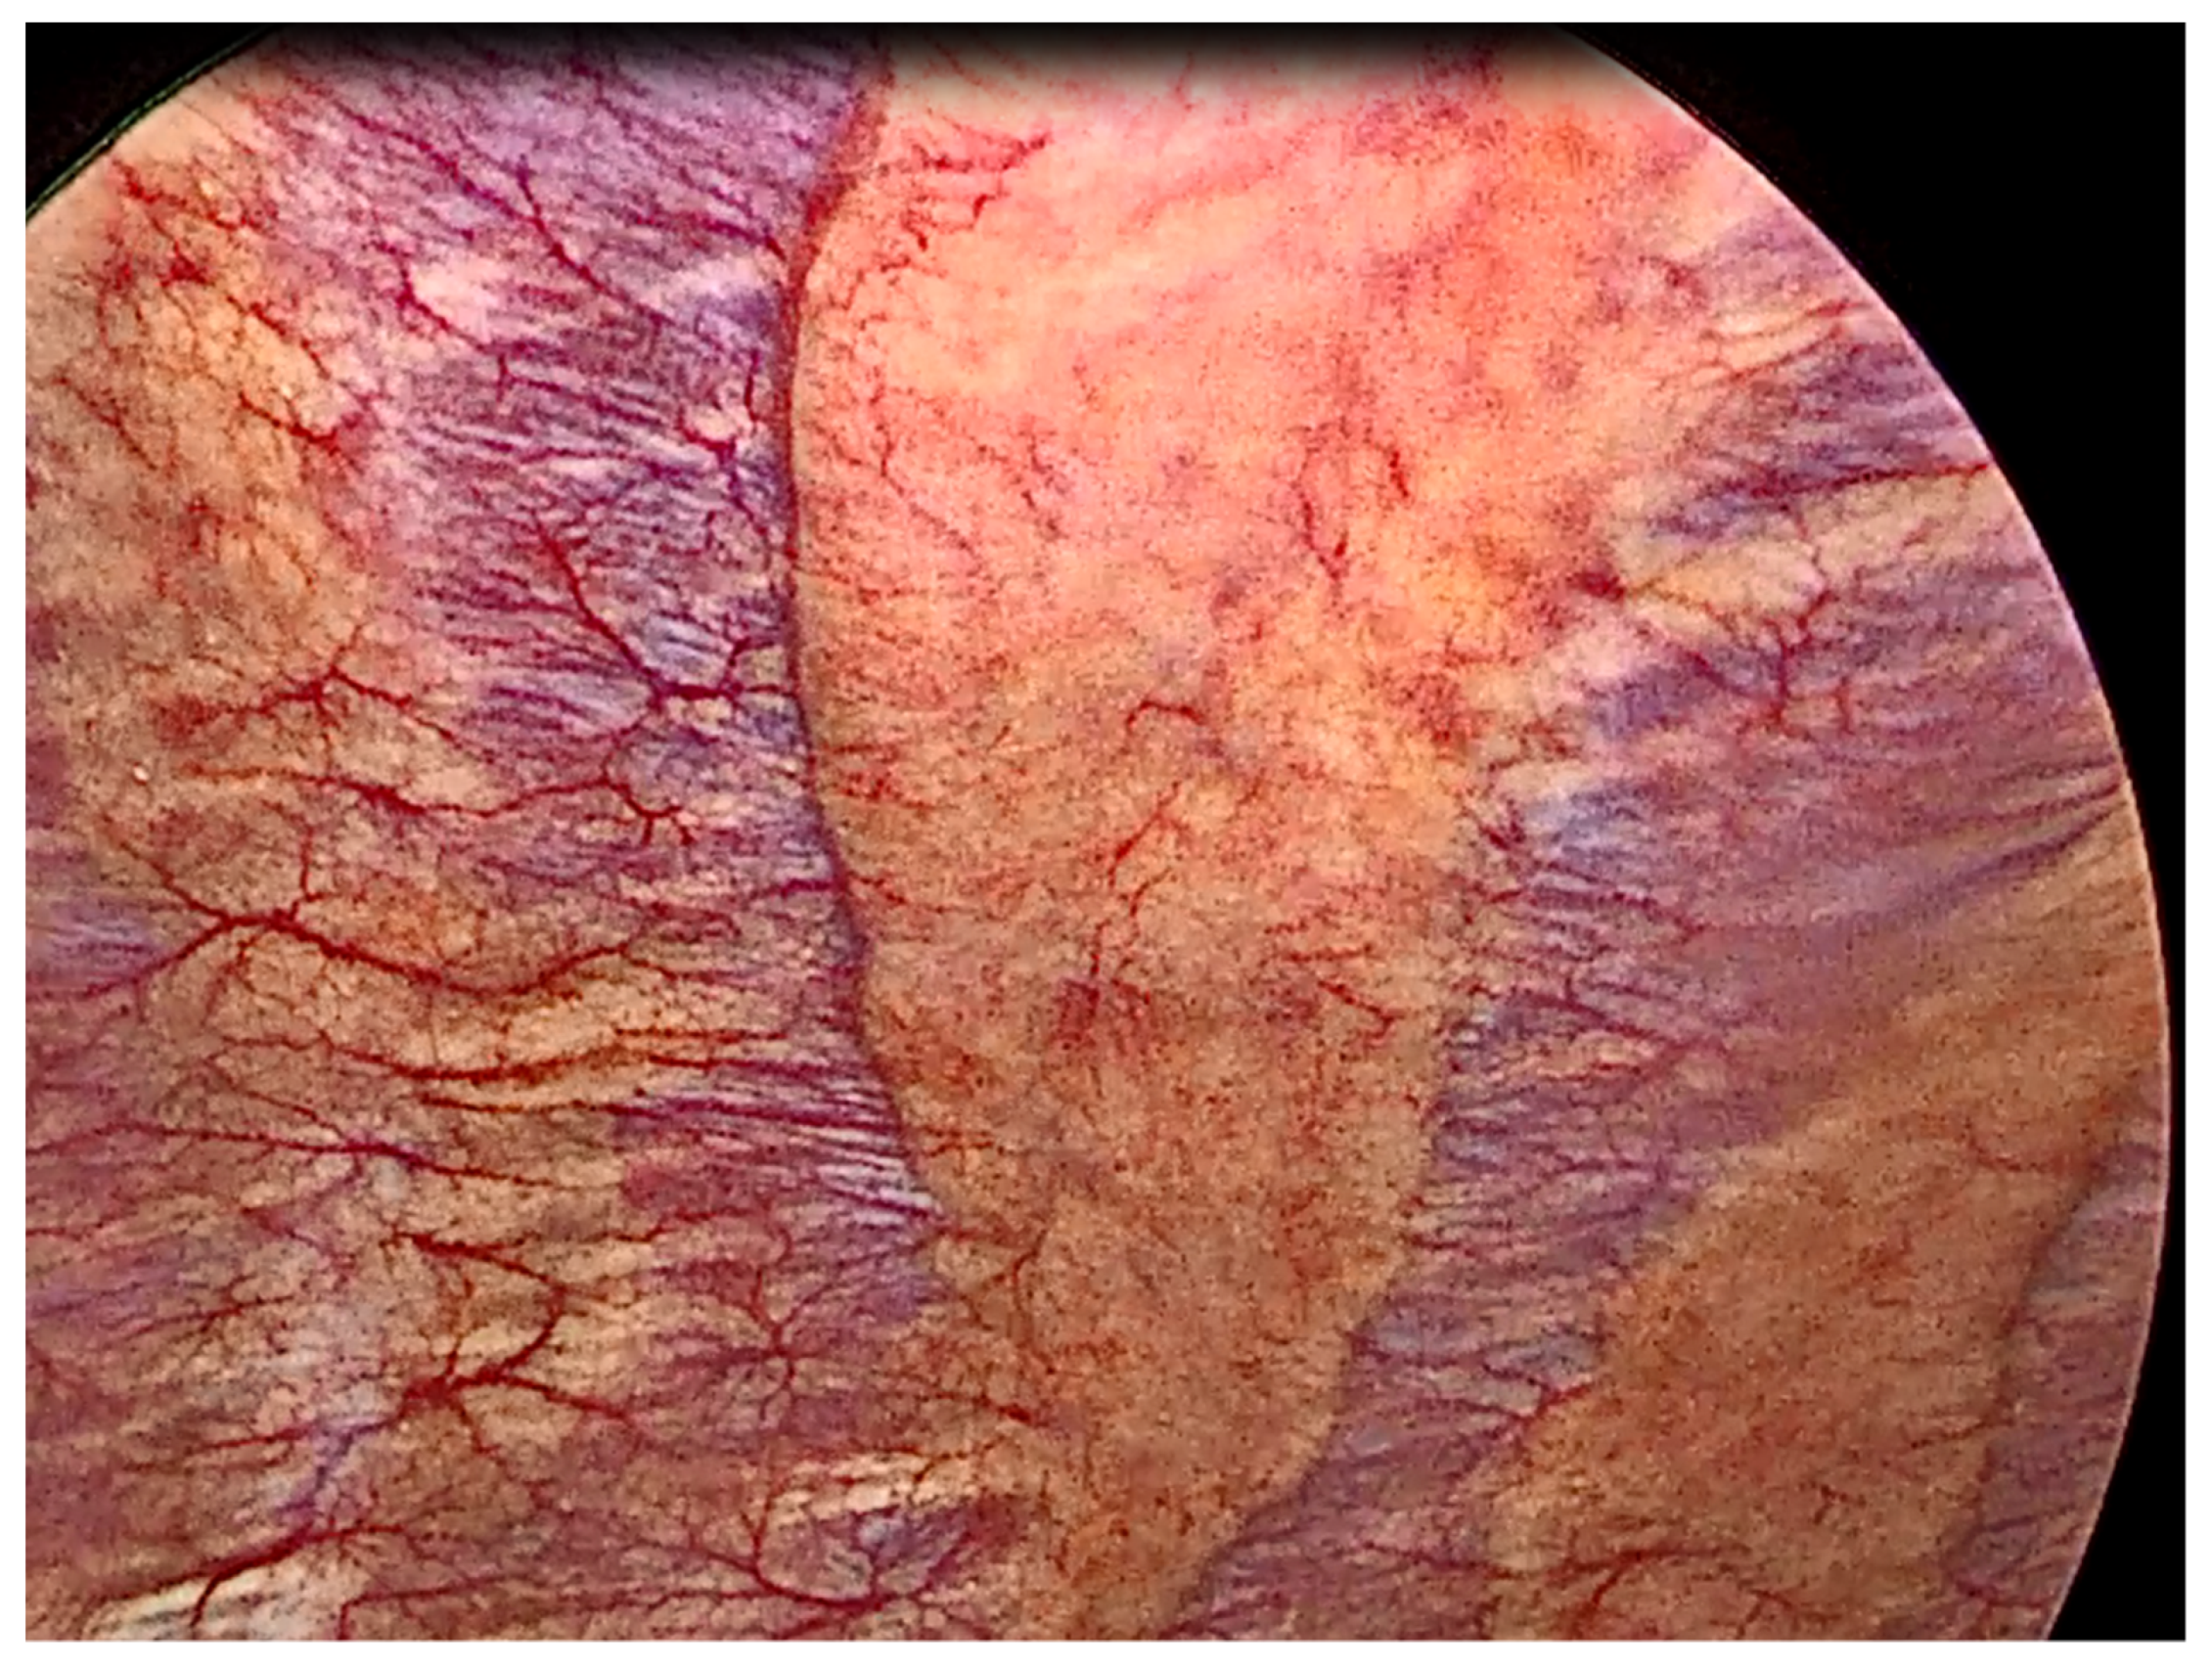

- Anevlavis, S.; Varga, C.; Nam, T.H.; Man, R.W.C.; Demetriou, A.; Jain, N.; Lanfranco, A.; Froudarakis, M.E. Is there any role for thoracoscopy in the diagnosis of benign pleural effusions. Clin. Respir. J. 2019, 13, 73–81. [Google Scholar] [CrossRef]